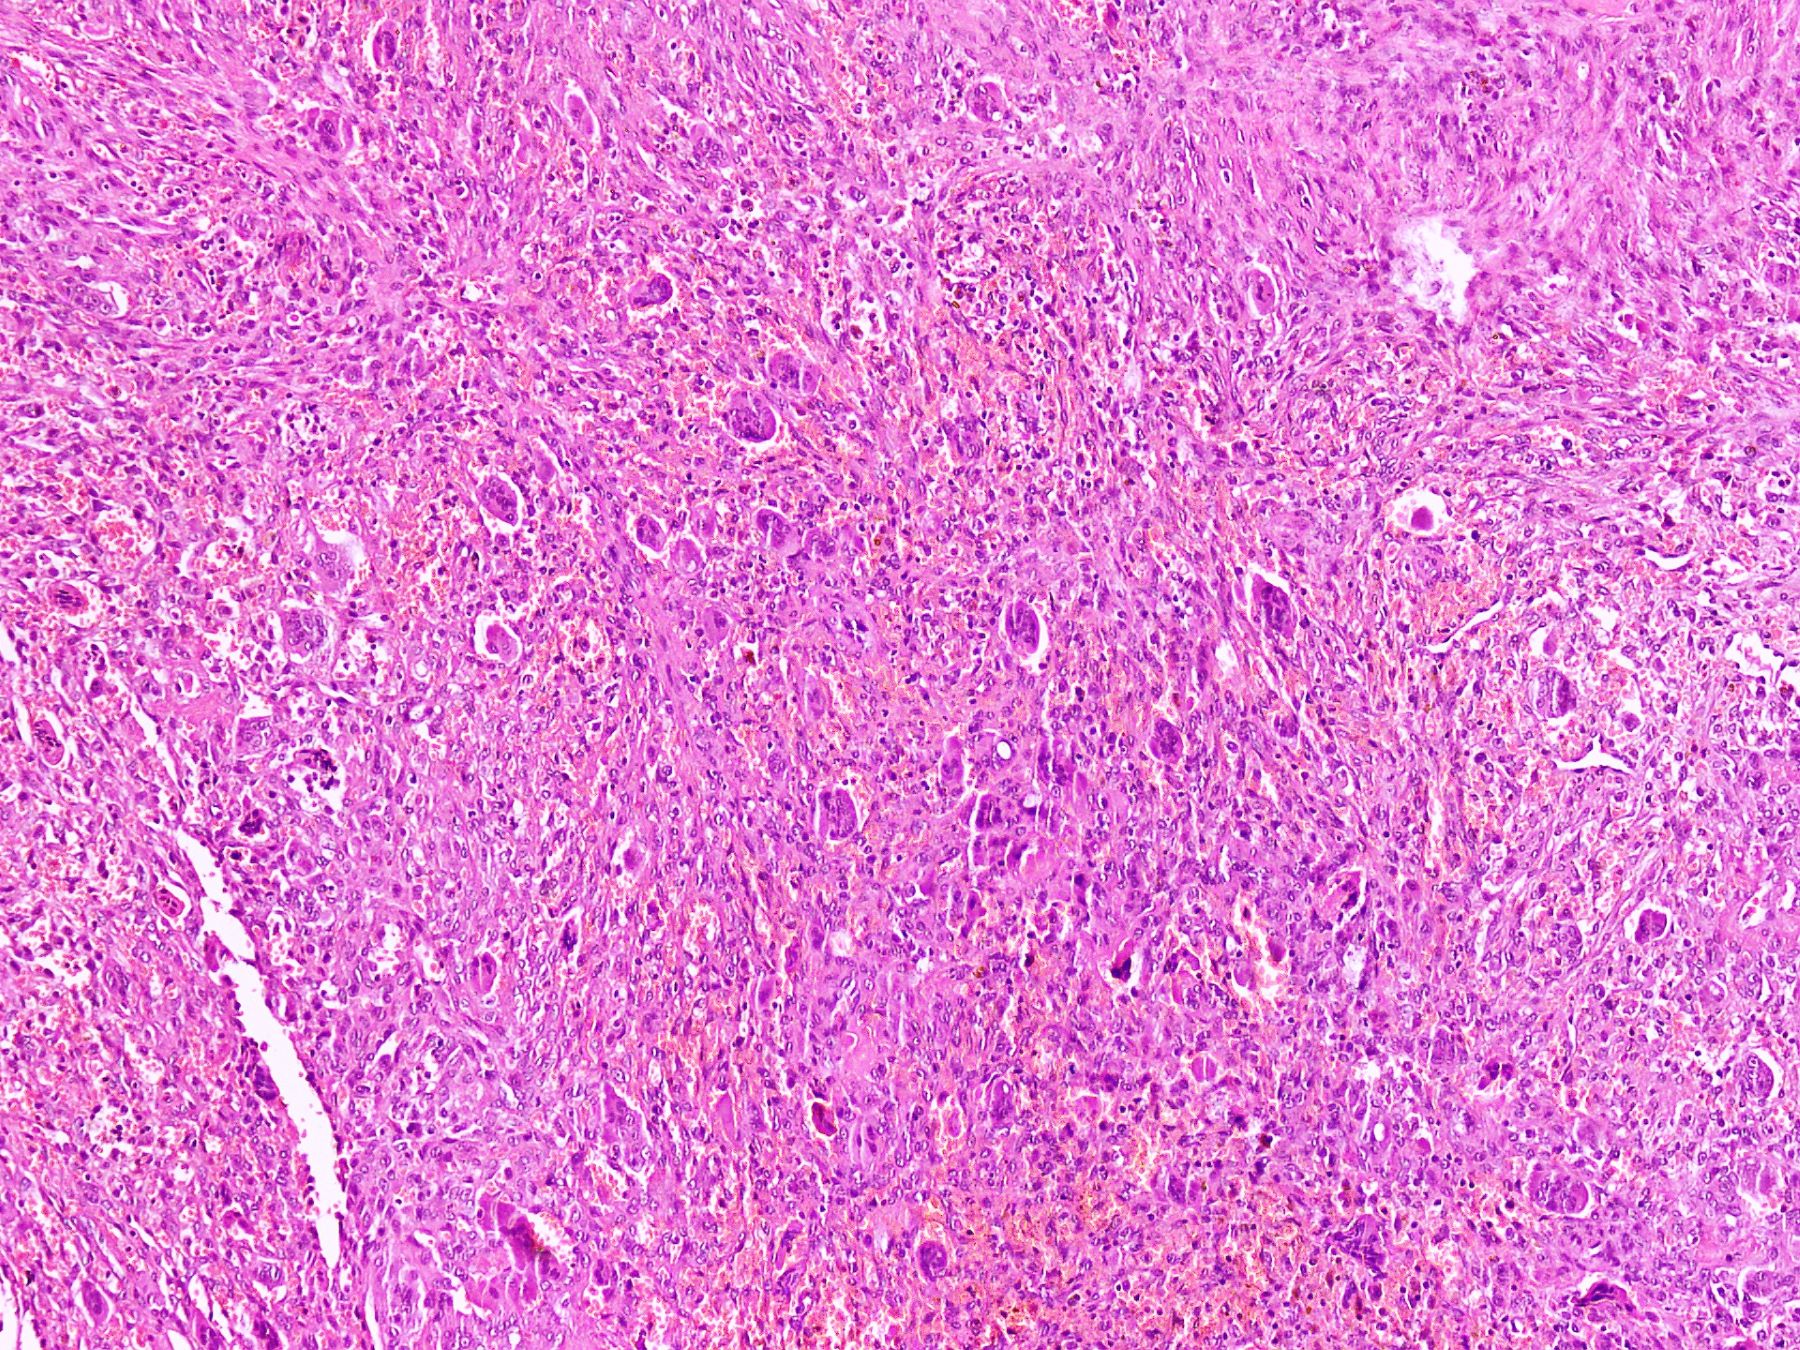

Microscopic (histologic) description

- Lobular pattern composed of groups and clusters of osteoclast-like multinucleated giant cells

- Vascular fibroblastic stroma

- Hemorrhage and hemosiderin deposits

- Tunneling resorption of adjacent uninvolved bone (J Int Oral Health 2015;7:50)

Microscopic (histologic) images

B. Brown tumor of hyperparathyroidism. The photomicrograph shows a lesion composed of bony trabeculae showing resorption along with scattered osteoclast-like giant cells in a vascularized spindled stroma. These microscopic findings with above mentioned clinical and radiological features are characteristic of brown tumor of hyperparathyroidism. Aneurysmal bone cyst affects young adults and shows large blood filled spaces with intervening septae containing fibroblasts and giant cells. Central giant cell granuloma produces radiolucent lesions in children and young women and shows osteoclast-like giant cells near hemorrhagic areas, cellular vascular and fibrous stroma and new bone formation at edge of lesion. Cherubism shows bilateral involvement of mandible and maxilla in young individuals and histology is similar to central giant cell granuloma. Giant cell tumor rarely affects mandible and shows uniform distribution of osteoclast type giant cells among mononuclear cells.

D. End stage renal disease. The photomicrograph shows a lesion composed of scattered osteoclast-like giant cells in a vascularized spindled stroma characteristic of brown tumor of hyperparathyroidism. End stage renal disease causes decreased glomerular filtration due to reduced nephron function, which results in decreased synthesis of 1,25 dihydroxyvitamin D3 by the kidney. This leads to decreased absorption of calcium by the gut. Consequently, there is an increased level of serum phosphate. Increased serum phosphate causes serum calcium to be deposited in bone, also leading to a decreased serum calcium. In response to low serum calcium levels, the parathyroid glands secrete increased parathyroid hormone, which results in secondary hyperparathyroidism.